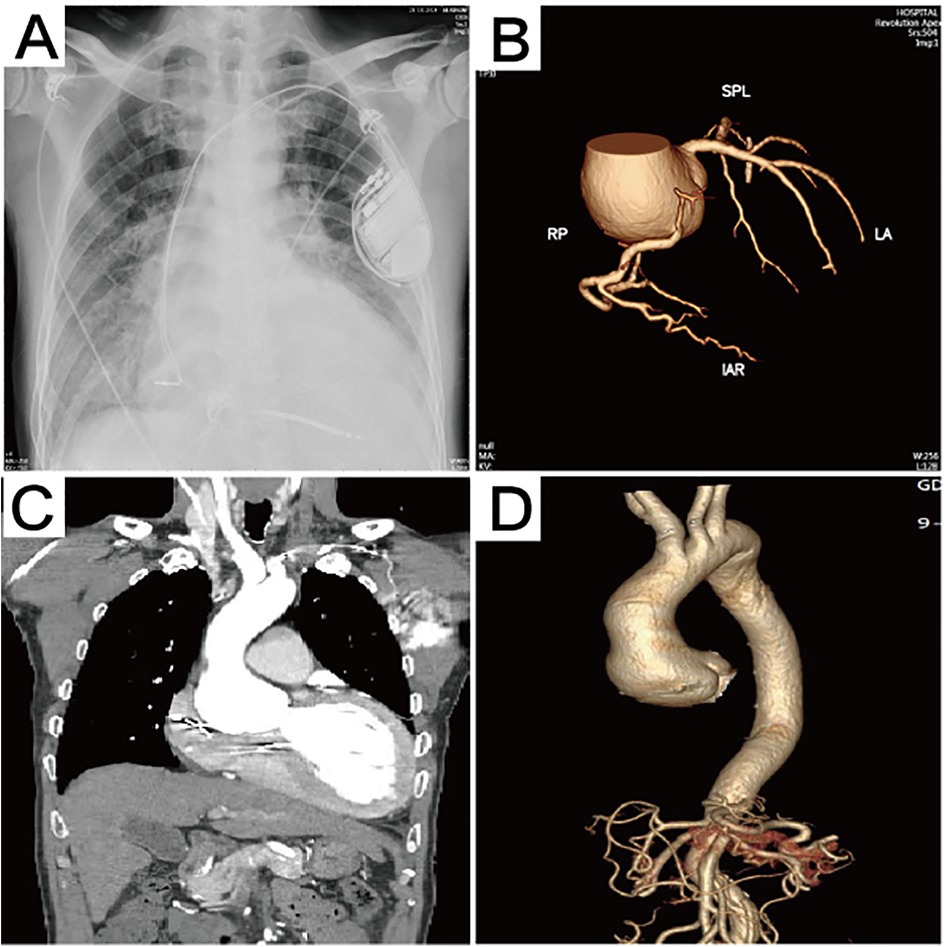

Figure 1

Preoperative imaging data. (A) The chest x-ray revealed the presence of pulmonary edema. (B) Computed tomography 3D reconstruction of the coronary arteries. (C) Preoperative computed tomography scan showing aortic sinus aneurysm, with the maximum aortic root diameter measuring 53.3 mm. (D) Computed tomography 3D reconstruction of the aorta.

Echocardiography after admission revealed dilated cardiomyopathy, severe aortic regurgitation, mild-to-moderate mitral regurgitation, moderate tricuspid regurgitation, reduced left ventricular systolic function, and general reduction in ventricular wall motion, with an ejection fraction of 22% and a left ventricular end diastolic diameter (LVEDD) of 80 mm. Coronary computed tomographic angiography (CTA) suggested the presence of varying degrees of mild stenosis in all coronary arteries, with no significant lesions identified (Figure 1B). Aortic CTA suggested an aortic root aneurysm, with a maximum aortic diameter of up to 53 mm (Figures 1C,D). Right heart catheterization showed a central venous pressure (CVP) of 3 mmHg, mean pulmonary artery pressure of 29 mmHg, and a total pulmonary resistance of 1.35 Wood units.